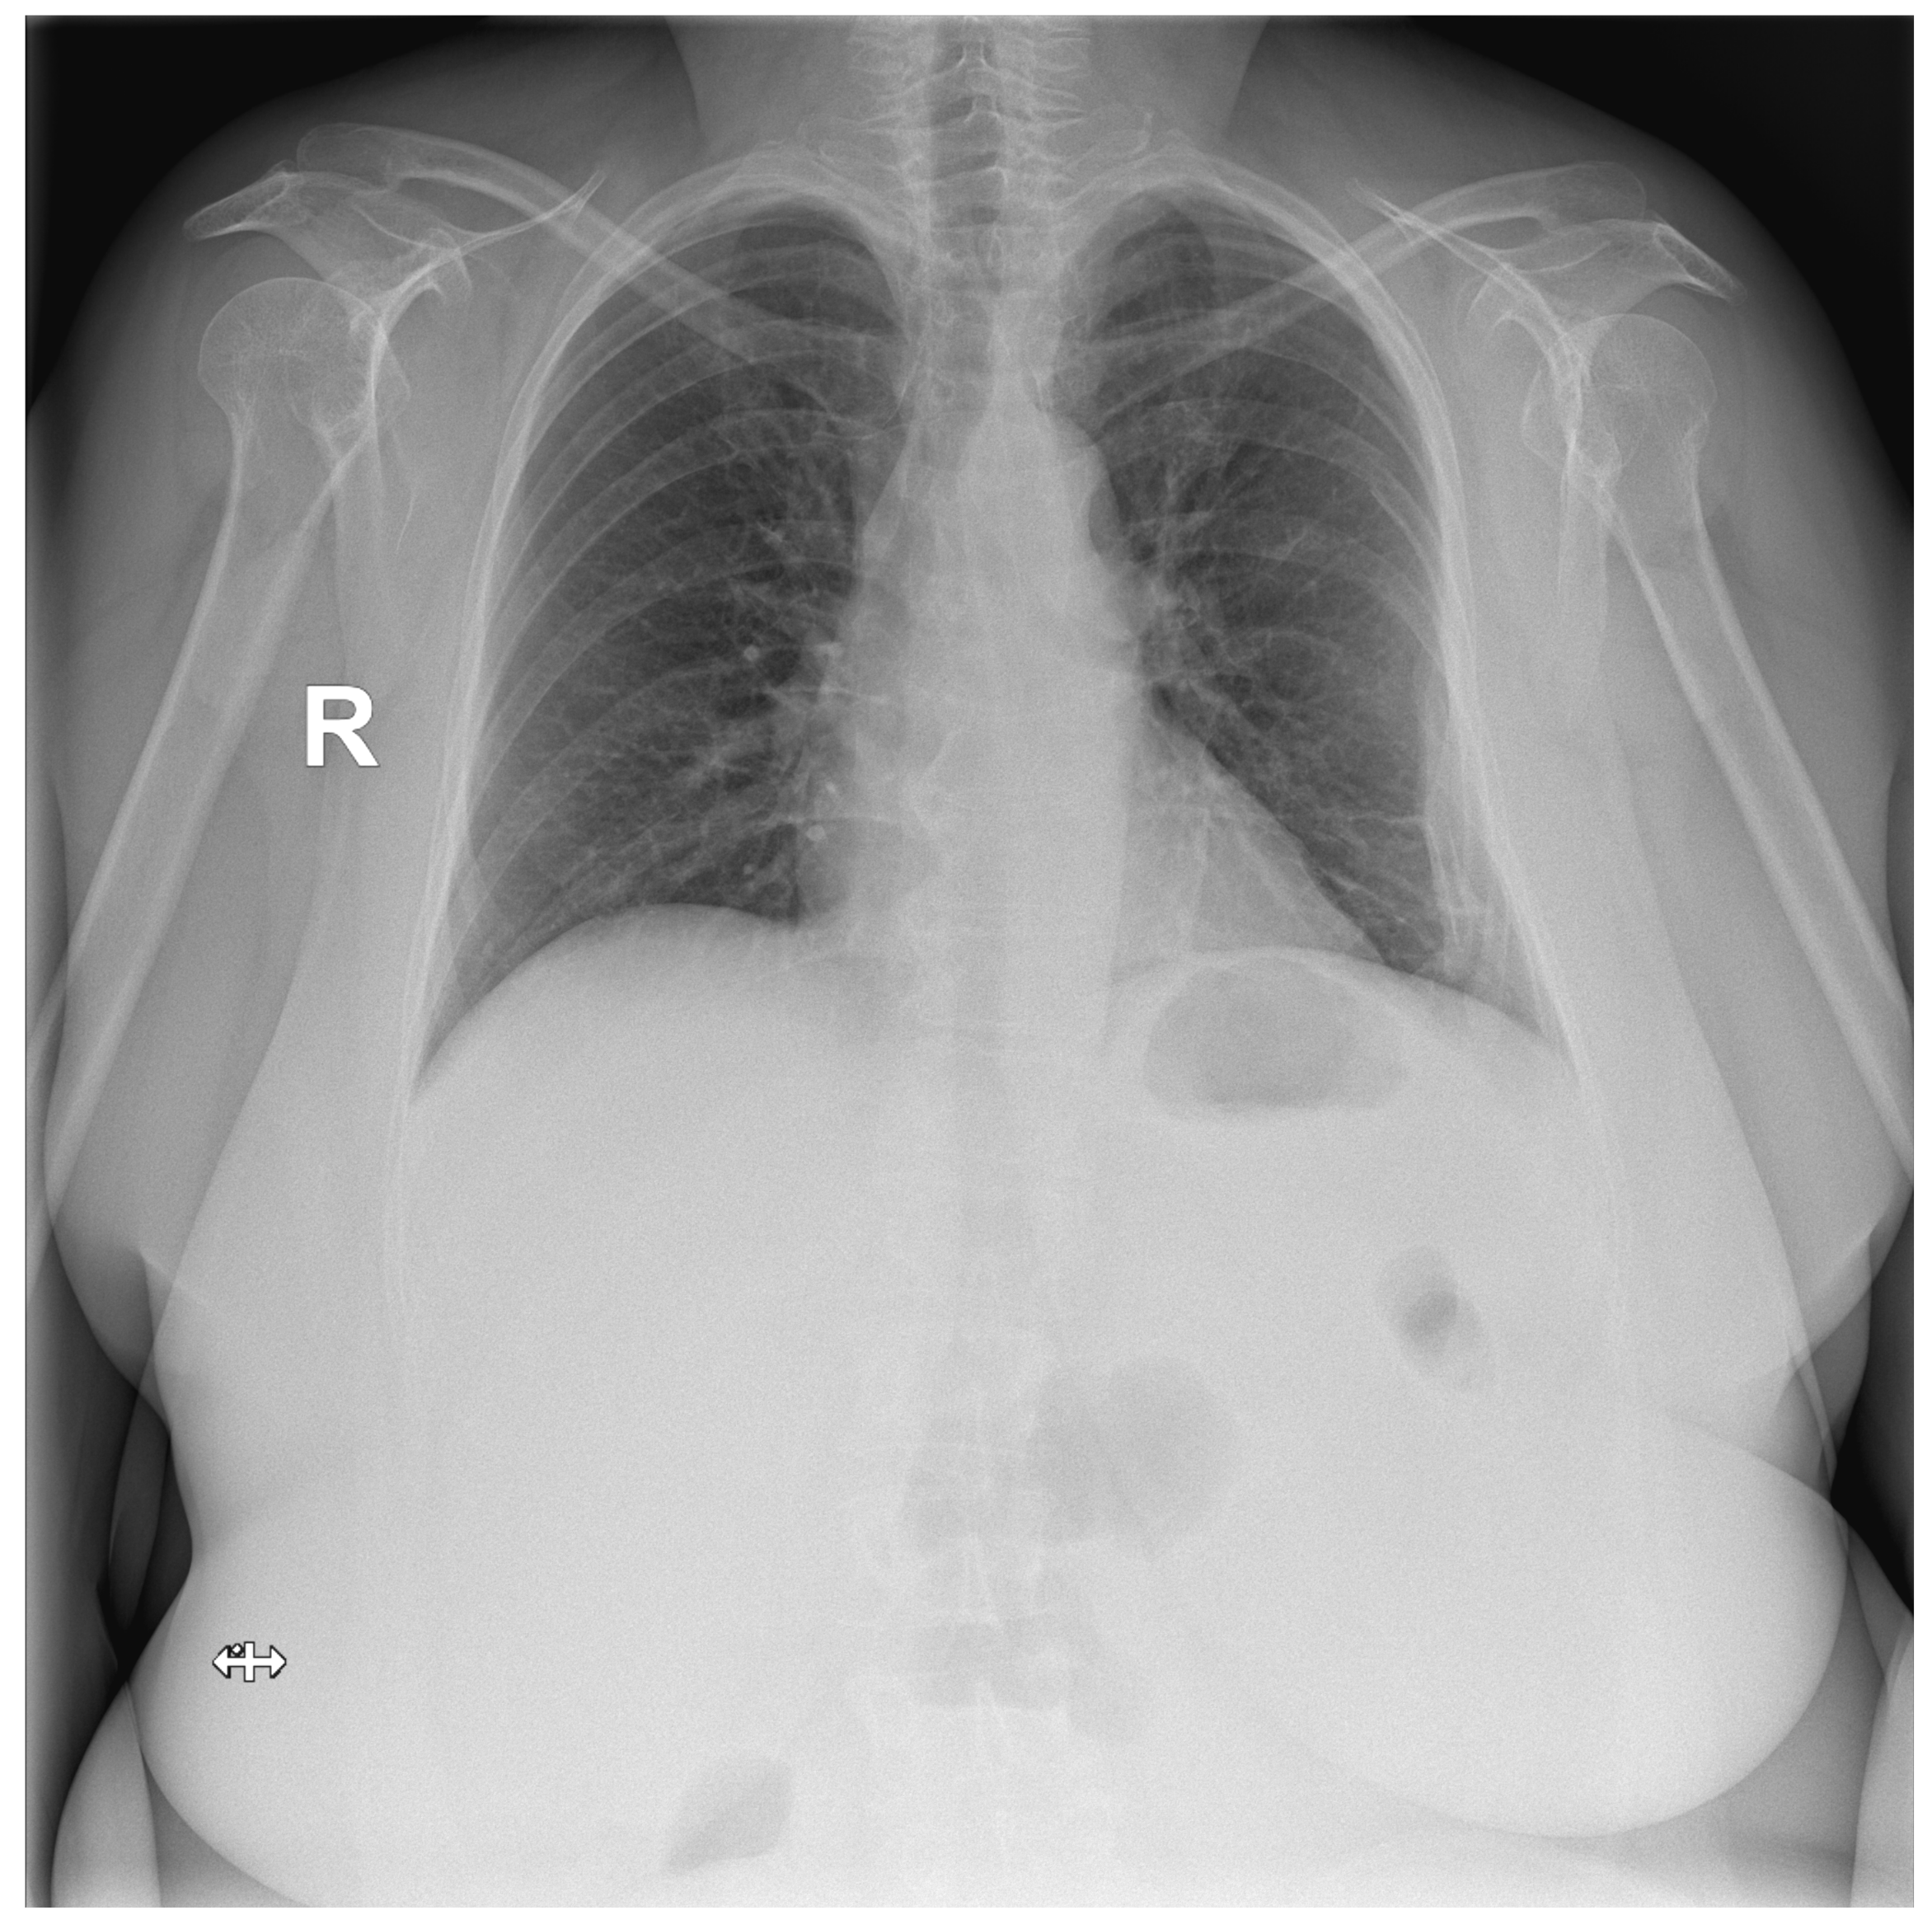

For the initial internal test, we used 397 CXRs that were not observed during the model training. Selected images were retrospectively assessed by three independent radiologists. The ground truth was determined by 100% agreement. The results of the internal test are shown in Table 1. Figure 2 shows an image involving a rib fracture that DLAD incorrectly classified as a scan without any abnormality.

Figure 2.

Confusion matrix and a false negative image that DLAD incorrectly classified as a true negative during the internal test. The CXR scan in high quality can be found in the Appendix A (Figure A1).